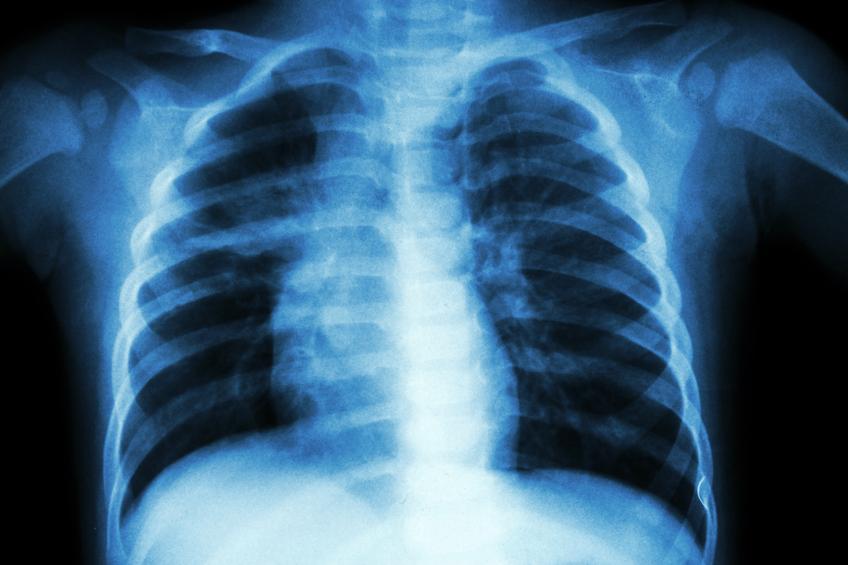

Según la anatomía humana, los 37 huesos del tórax son los siguientes:

Las costillas

Hay un total de 24 costillas, concretamente encontramos 12 en cada lado, que son huesos largos, planos y curvados, cuya función principal es proteger a los órganos vitales de posibles golpes desde cualquier ángulo pero, sobre todo, por los costados puesto que en los laterales son los únicos huesos que tenemos. Las costillas se unen entre ellas por los cartílagos intercostales, que les ayudan a moverse para facilitar la respiración. Además, se juntan por la parte delantera al esternón gracias a los cartílagos costales y por la parte de atrás, se conectan con la columna vertebral por las articulaciones costovertebrales.

Existen 3 tipos de costillas:

1. Las costillas verdaderas: son las 7 primeras costillas que hay a cada lado, se anclan tanto a las vértebras como al esternón y, por ello, son las costillas más fuertes y firmes.

2. Las costillas falsas: las 3 costillas que siguen a las verdaderas en cada costado, son las conocidas como falsas, llamadas así porqué están unidas directamente con las vértebras y al esternón se unen de forma indirecta, a través de una extensión del cartílago. Por lo tanto, este tipo de costillas son mucho más móviles que las verdaderas.

3. Las costillas flotantes: estas siguen a las falsas, encontramos 2 a cada lado y se las llama flotantes por el hecho de estar solo unidas a las vértebras, ya que al esternón no se unen de ninguna forma.

El esternón

Es un hueso plano que suele medir unos 15 centímetros de longitud y que se encuentra situado en la parte frontal del tórax, conectando las costillas y protegiendo a los órganos vitales por delante. Este hueso está subdividido en 3 partes:

1. El manubrio: parte superior del esternón por la cual se une la primera costilla verdadera de cada lateral y, a su vez, se articulan los huesos de la clavícula, siendo este el punto de unión del tórax con las extremidades superiores.

2. El cuerpo del esternón: es la parte más grande del esternón y se encuentra justo en el medio unido al resto de costillas verdaderas directamente y a las falsas indirectamente.

3. La apófisis xifoides: parte inferior del esternón que normalmente tiene forma de punta pequeña aunque, a veces, su forma puede variar. Durante muchos años de nuestra vida es un cartílago, pero se va osificando hasta ser completamente un hueso en la edad adulta. Además, es la única parte del esternón que no está unida a ninguna costilla.

Las vértebras torácicas

Son las vértebras con menor movilidad y más grandes que hay, se encuentran a continuación de las cervicales, que conectan con la cabeza, y antes de las lumbares, que se unen con la pelvis y las extremidades inferiores. Por lo tanto, estas 12 vértebras torácicas o dorsales están en la parte media de la columna vertebral yse unen a las costillas gracias a su articulación. Se denominan con una T delante que indica que pertenecen a la región torácica, por lo que encontramos las vértebras desde la T1 hasta la T12.